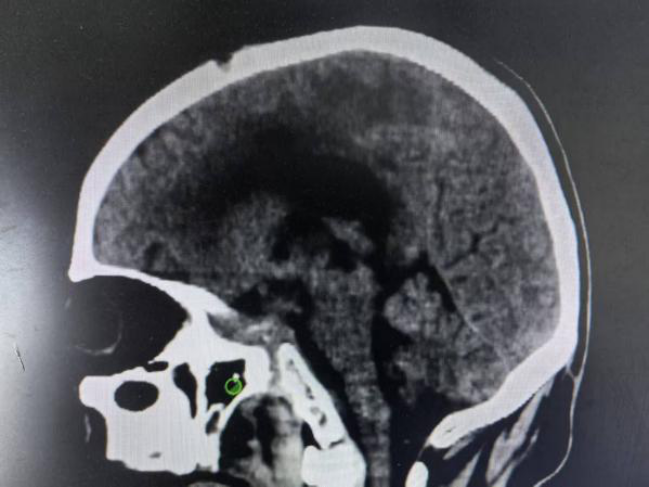

两个月前,56岁的刘先生(化名)在家中突然倒地,被紧急送入常德市第二人民医院。头颅CT检查结果触目惊心:丘脑出血破入脑室,且血肿堵塞了脑脊液循环的要道——第三脑室,形成了“塑性”状态。这意味着,不断增多的脑积水正在像“水锤”一样,无情地压迫着刘先生的大脑深处。

手术前头部CT